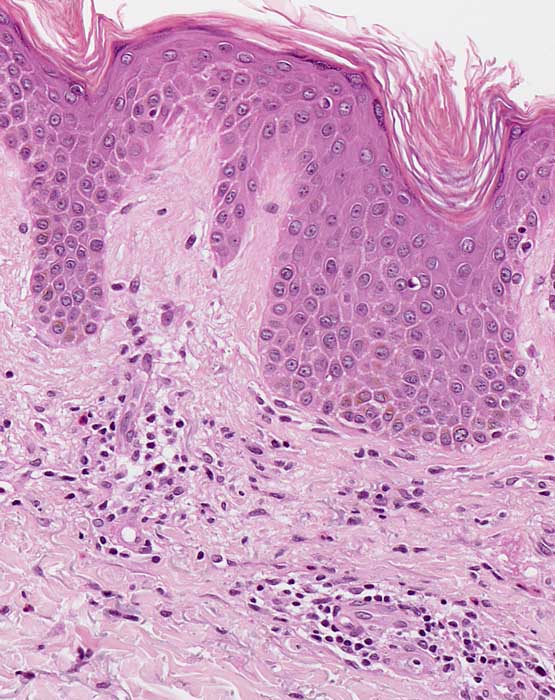

PathoPic – image database / PathoPic ID 7602 - Chronisches Ekzem

Kompakte Hyper-Orthokeratose. Unregelmässige psoriasiforme Epidermishyperplasie und diskrete Spongiose. Oberflächlich dermales perivaskulär betontes Entzündungsinfiltrat mit Beteiligung einzelner eosinophiler Granulozyten. Geringe Fibrose der papillären Dermis.

Chronische Kontaktdermatitis.

Histologie

200